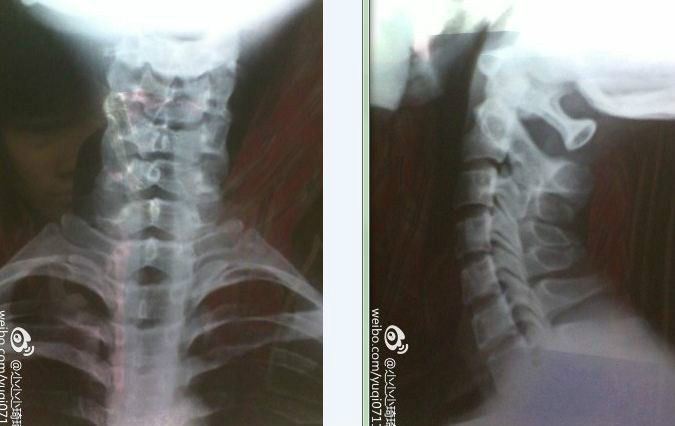

7岁女孩颈椎反张失稳x片